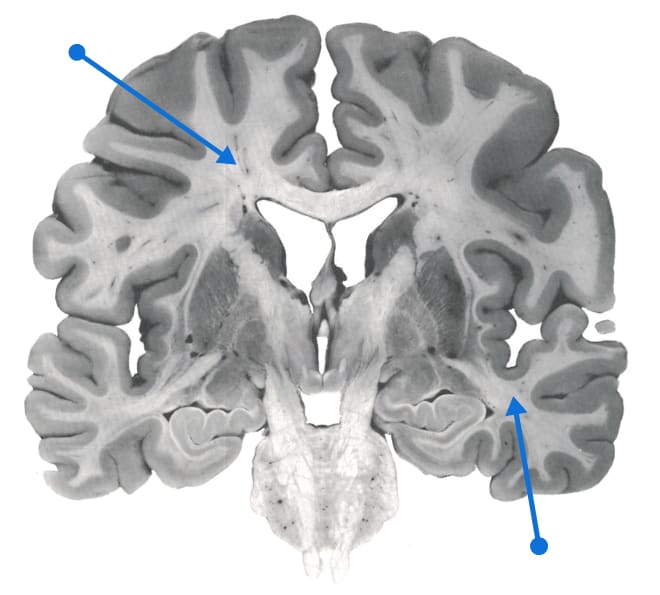

Source: https://www.neuromedia.ca/white-matter/

Half of the human brain is white matter, i.e. neuronal axons with fatty sheaths around them to make them transmit signals faster. White matter is ~1/10 the volume of rodent brains, but ~1/2 the volume of human brains. Wiring is expensive and gets minimized; see "Principles of Neural Design" by Sterling and Laughlin. All these long-range axons are a huge metabolic expense. That means fast, long-range, high bandwidth (so to speak——there are many different points involved) communication is important to cognitive capabilities. See here.